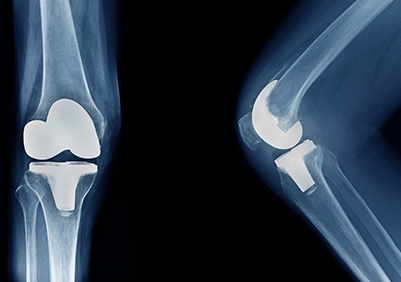

Knee Replacement

If you suffer from restricted mobility in the knee, you may be a candidate for knee replacement surgery.

Joint Replacement

If you suffer from restricted mobility or joint pain you may be a candidate for joint replacement surgery.